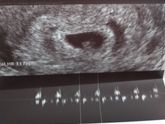

Сегодня была на первом узи. Срок 6,1 неделя. Очень рада что услышала сердцебиение 117уд/мин. Через неделю нужно сходить на контроль и можно вставать на учёт.